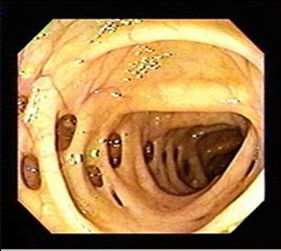

Εικόνα 2.

Εκκολπώματα ως τυχαίο εύρημα κατά την κολονοσκόπηση